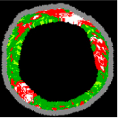

Since clustering algorithms will not return the same cluster index value every time, the colour of each cluster should be determined. With respect to the colour of each cluster, its matching plaque components can be determined as NC: red, DC: white, FI: dark green, and FF: light green [45].

The result of the clustering algorithms will be strongly affected by the presence of outliers that do not belong to any of the clusters [28]. The purpose of outlier detection is to find small groups of pixels that are not similar to the rest of the pixels belonging to the same cluster [72]. Figure 5 illustrates the outliers with dark green, light green, etc., in an NC image. The zoomed area (b) is indicated by the blue box in the original image (a).

Figure 5.

Outliers in an NC image: (a) original image, and (b) zoomed area.

To provide more reliable results, outliers should be removed from the generated clusters. NC and DC images play an important role in TCFA detection; therefore, their outliers are removed for modifying the training set. First, the Euclidian distance between pixels belonging to the NC and its centre are calculated. Then, for each pixel in the NC image, if its distance is greater than the defined threshold value (TNC), then this pixel is an outlier, and its intensity should be replaced with zero. Based on the sub experiments, the value of TNC is changed, and intra-cluster distance (the distance between pixels and the centroid within a cluster) for the NC image are calculated. The value of TNC = 200 gave the best result for the minimum distance between pixels of the NC and its centre. In addition, outliers of DC image are removed in the similar way [45].